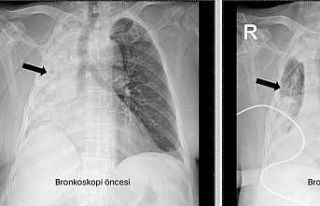

Nefes borusuna kaçan mısır tanesi 5 ay sonra ortaya...